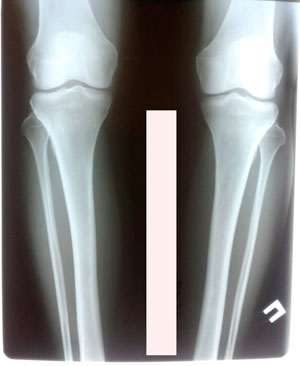

рентген в 60 дней

IMG_4850-06-08-19-08-10.JPG

IMG_4849-06-08-19-08-10.JPG